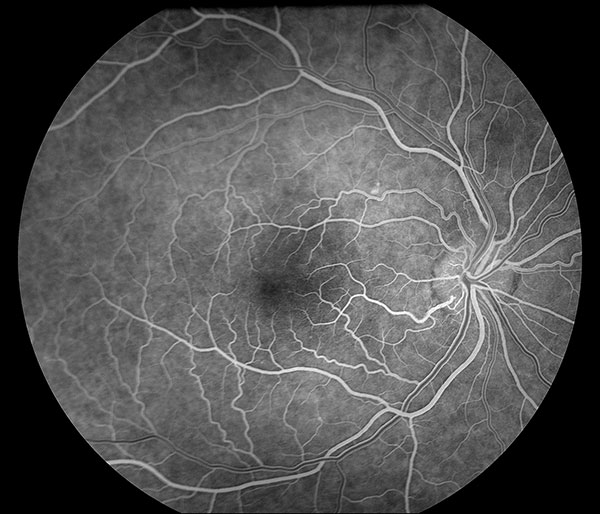

Флюоресцентная ангиограмма нормального глазного дна

Флюоресцеин поступает в глаз через 6-12 с после инъекции. Первая флюоресценция хориоидеи — слабая, неравномерная, пятнистая, т.н. пятнистое хороидальное заполнение. В течение следующих 10 с (20-25 с после инъекции) ангиограмма становится светлой, что обусловлено заполнением флюоресцеином хориокапилляров. В большинстве случаев флюоресцеин оказывается в хориоидее на 1-2 с раньше начала поступления красителя в артерии сетчатки. Заполнив ретинальные артерии, краситель следует в артериолы, капилляры, посткапиллярные венулы и, наконец, в вены. Поскольку в венах скорость тока крови в центре и пристеночно разная, заполнение вен флюоресцеином характеризуется «ламинарным током», в течение 5-10 с начальная венозная фаза переходит в развитую. В диске зрительного нерва гиперфлюоресценция начинается в начальную венозную фазу. Через 30 с после инъекции высота концентрации флюоресцеина начинает спадать. Спустя 3-5 мин после инъекции сосуды хориоидеи и сетчатки освобождаются от флюоресцеина, через 10 мин флюоресцеин полиостью вымывается из сосудистой циркуляции.

Пигментный эпителий полупрозрачен и частично экранирует свечение хориоидеи, контрастируя феномены флюоресценции сосудов прозрачной в норме сетчатки. При интенсивной пигментации рисунок сосудов сетчатки просматривается хорошо, хориоидальные сосуды плохо различимы. В случае слабой пигментации глазного дна контрастность флюоресцентных ангиограмм сильно снижается, хорошо видны сосуды хориоидеи, различимость капилляров сетчатки резко ухудшается. В макулярной области сосудистая оболочка обычно содержит повышенное количество меланина, по этой причине интенсивность свечения желтого пятна сильно ослаблена.

Фазы циркуляции красителя. В соответствии с этапами заполнения сосудистого русла сетчатки выделяется большое количество фаз исследования. В практической работе используются следующие:

- артериальная фаза — длится приблизительно с 10-й по 13-ю с от момента введения красителя, от начала до окончания прокрашивания артериол. Заполнение сосудистой оболочки (хориоидальная фаза) на 0,2-0,5 секунд предшествует по времени заполнению артерии и может иметь сегментарный характер;

- артериовенозная фаза — с 15-й по 30-ю секунду исследования, — время заполнения венул. К концу этой фазы яркость свечения артериол и венул уравнивается. Концентрация флюоресцеина в сосудах сетчатки и хориоидеи достигает максимума, апогей свечения глазного дна;

- венозная фаза — обычно начинается на 30-35-й секунде, когда венулы сетчатки начинают флюоресцировать ярче артериол. При слабой пигментации глазного дна хорошо заметны темные хориоидальные сосуды на фоне интенсивно прокрашенных сосудистой оболочки и склеры;

- поздняя венозная фаза — начинается через 1-1,5 минуты, с момента повторного уравнивания яркости свечения артериол и венул. Интенсивность флюоресценции глазного дна снижается;

- фаза рециркуляции красителя (поздняя фаза) начинается с момента, когда сосуды на диске зрительного нерва становятся темнее его поверхности (через 10-15 минут). Время начала фазы существенно зависит от характеристики светофильтров фундус-камеры. Качество получаемых фотоснимков обычно снижено вследствие крайне слабого свечения глазного дна и накопления флюоресцеина во влаге передней камеры глаза.